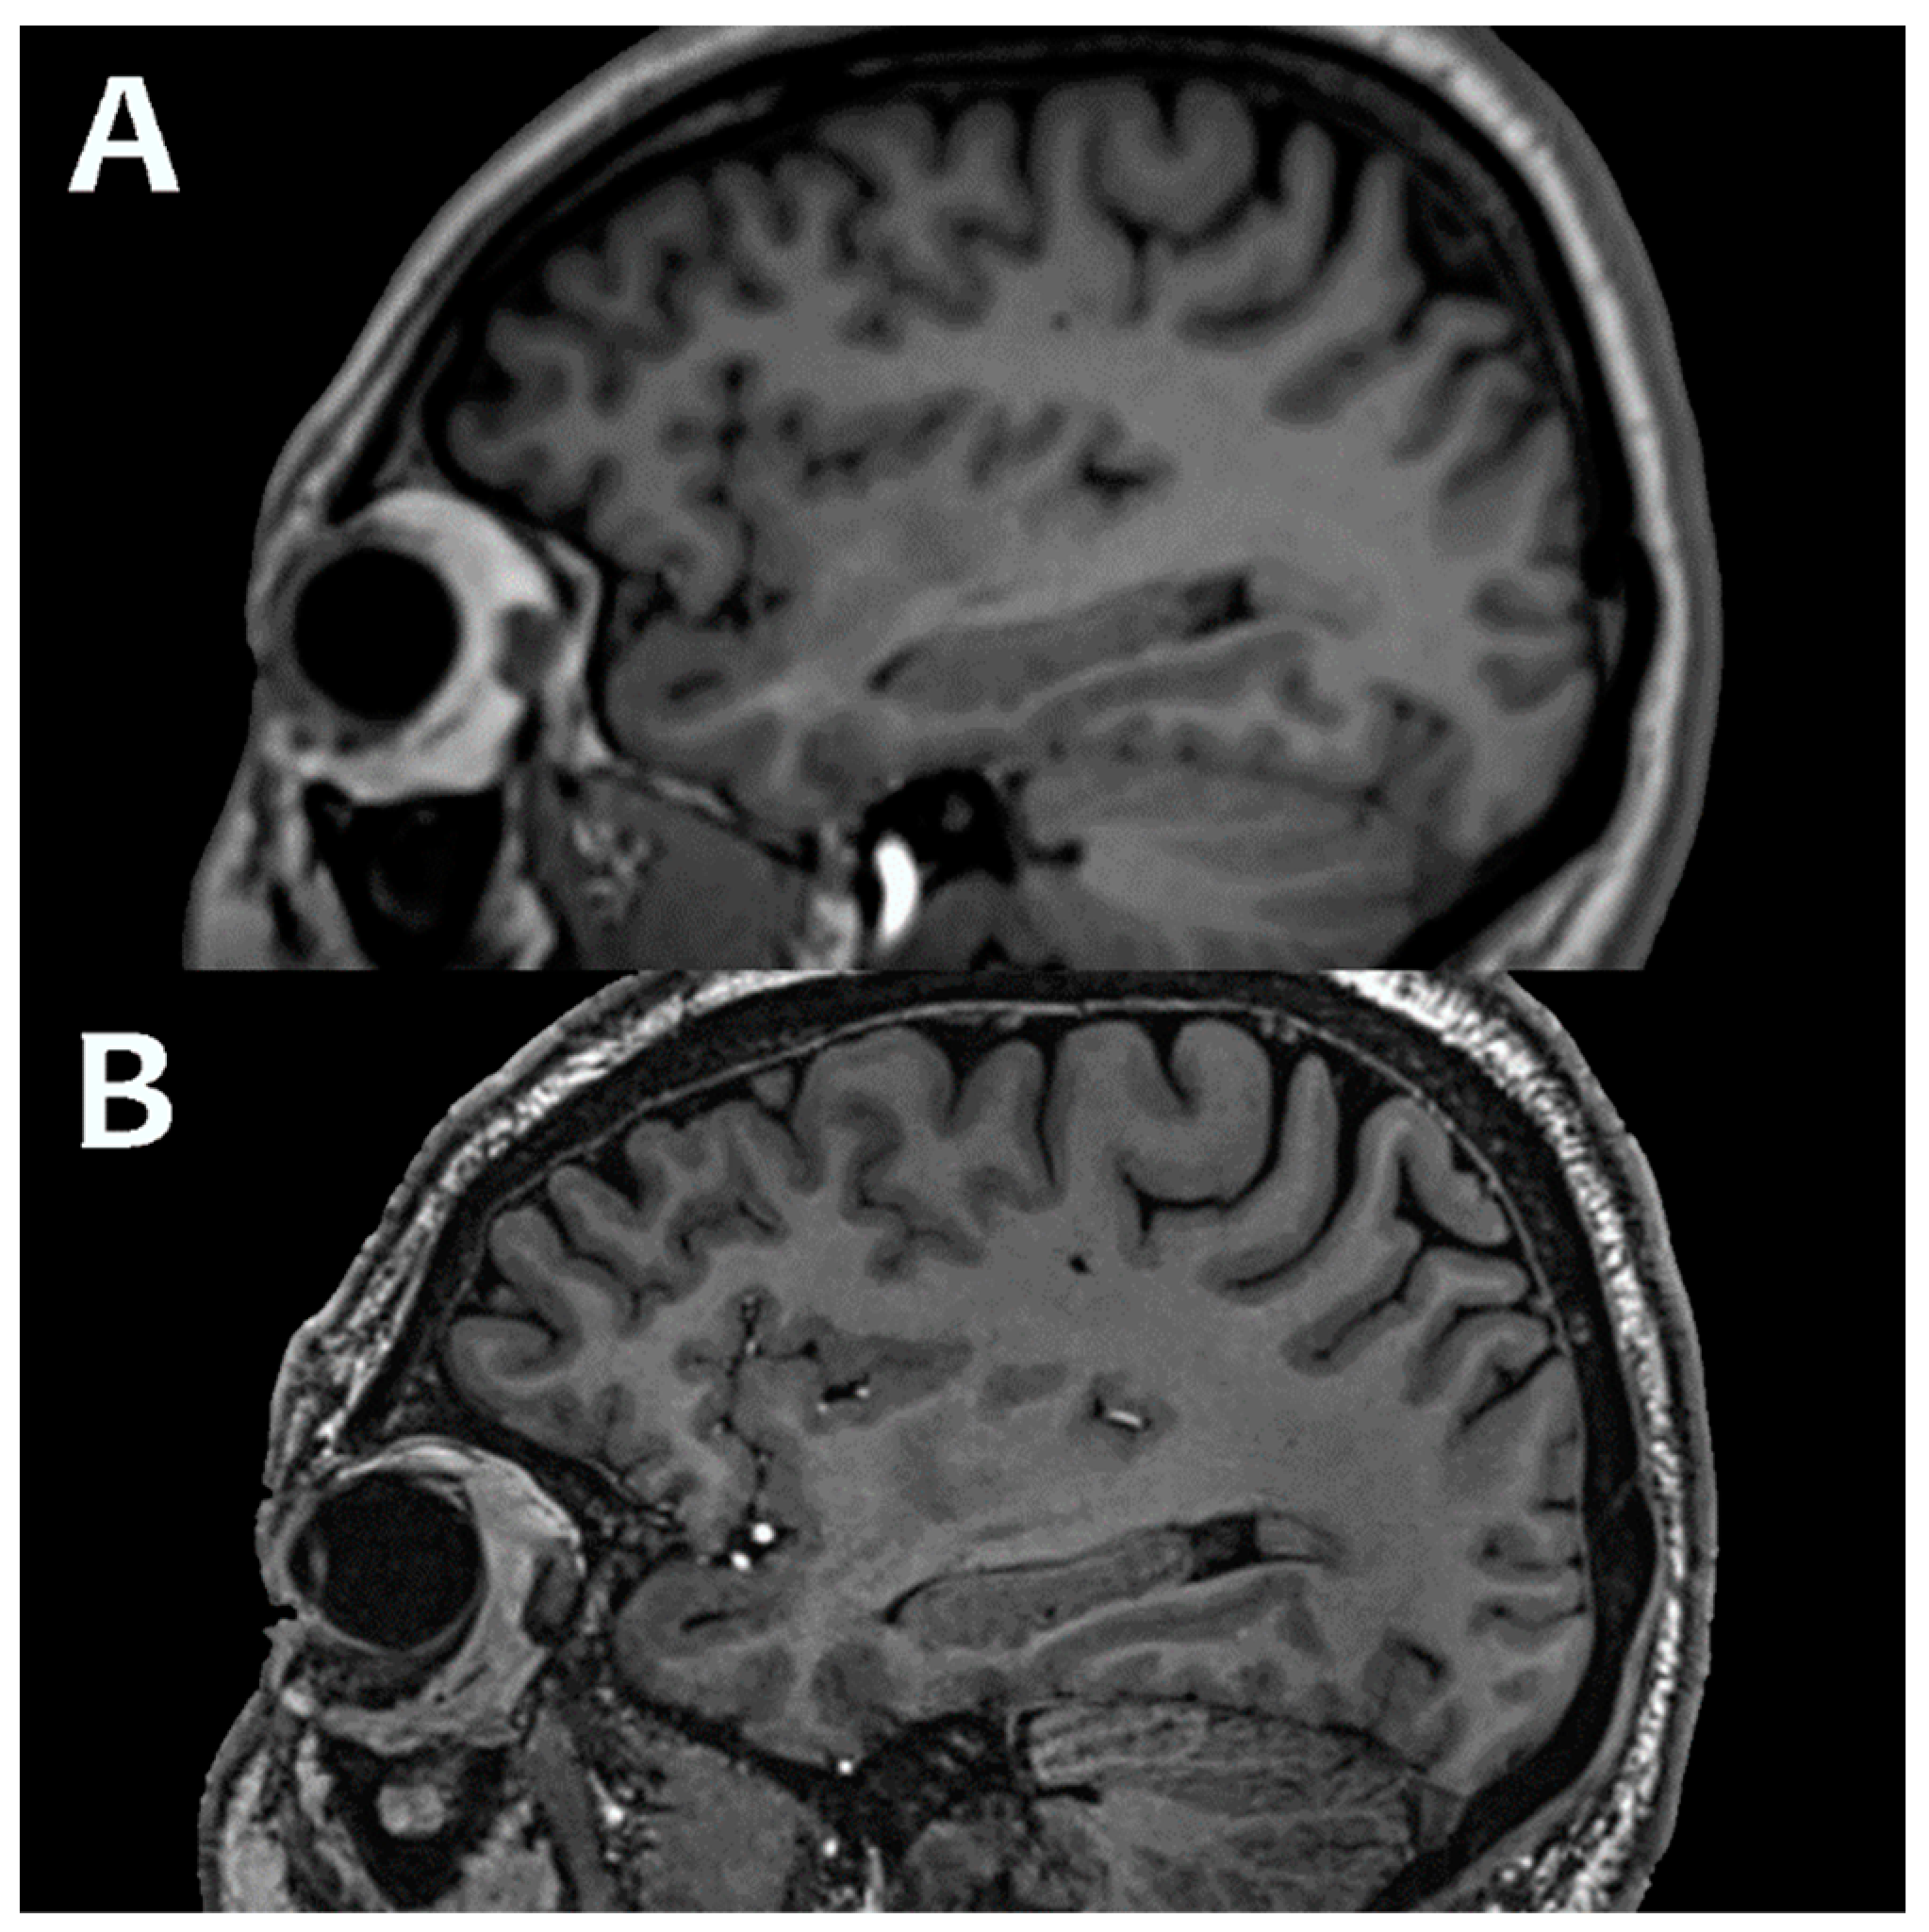

- Keith, G.A.; Woodward, R.A.; Hopkins, T.; Allwood-Spiers, S.; Trinder, J.; Muir, K.W.; Porter, D.A.; Fullerton, N.E. Towards clinical translation of 7 Tesla MRI in the human brain. IPEM-Translation 2024, 9, 100025. [Google Scholar] [CrossRef]

- Trattnig, S.; Springer, E.; Bogner, W.; Hangel, G.; Strasser, B.; Dymerska, B.; Cardoso, P.L.; Robinson, S.D. Key clinical benefits of neuroimaging at 7 T. NeuroImage 2018, 168, 477–489. [Google Scholar] [CrossRef]

- Veersema, T.J.; Ferrier, C.H.; van Eijsden, P.; Gosselaar, P.H.; Aronica, E.; Visser, F.; Zwanenburg, J.M.; de Kort, G.A.P.; Hendrikse, J.; Luijten, P.R.; et al. Seven tesla MRI improves detection of focal cortical dysplasia in patients with refractory focal epilepsy. Epilepsia Open 2017, 2, 162–171. [Google Scholar] [CrossRef]

- Okromelidze, L.; Patel, V.; Singh, R.B.; Chiriboga, A.S.L.; Tao, S.; Zhou, X.; Straub, S.; Westerhold, E.M.; Gupta, V.; Agarwal, A.K.; et al. Central Vein Sign in Multiple Sclerosis: A Comparison Study of the Diagnostic Performance of 3T versus 7T MRI. Am. J. Neuroradiol. 2023, 45, 76–81. [Google Scholar] [CrossRef]

- Özütemiz, C.; White, M.; Elvendahl, W.; Eryaman, Y.; Marjańska, M.; Metzger, G.J.; Patriat, R.; Kulesa, J.; Harel, N.; Watanabe, Y.; et al. Use of a Commercial 7-T MRI Scanner for Clinical Brain Imaging: Indications, Protocols, Challenges, and Solutions—A Single-Center Experience. Am. J. Roentgenol. 2023, 221, 788–804. [Google Scholar] [CrossRef]